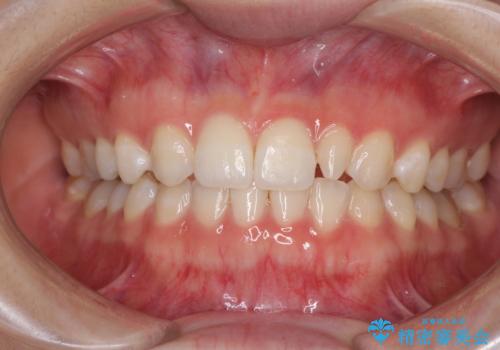

前歯の反対咬合 非抜歯のワイヤー矯正

海外転居前に気になる前歯を整えたい 上下前歯の部分矯正